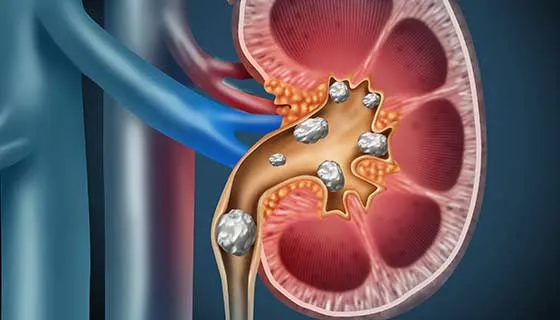

Diálise Peritoneal na Doença Renal Policística: existe algum motivo para não indicar?

A DRPAD não é contraindicação à DP — e, na prática, muitos pacientes têm resultados comparáveis à hemodiálise. O “porém” está na mecânica: rins/hepatomegalia podem reduzir tolerância a volumes, aumentar risco de hérnias e extravasamentos, e piorar desconforto respiratório. Com técnica adequada (cateter presternal ou lateral, volumes menores, cicladora noturna e decúbito supino), a maioria das barreiras é contornável. Neste post, revisamos quando a DP é ótima, quando exigir cautela e como ajustar a prescrição para segurança e qualidade de vida.